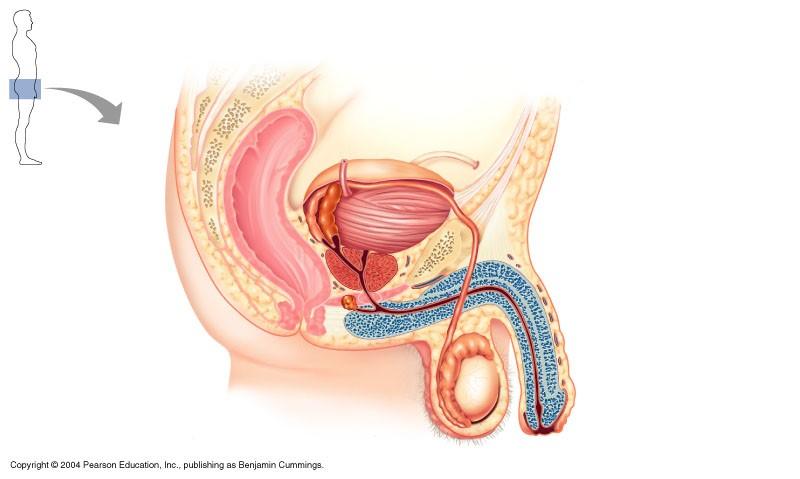

The structure indicated in the diagram below of the male reproductive system is

epididymis

The structure indicated in the diagram of the male reproductive system is the ejaculatory duct

false

The structure indicated in the diagram of male reproductive system is epididymis

false

Male reproductive system

ampulla of ductus deferens

vas deferens

prostate

epididymis

testes

male reproductive structure